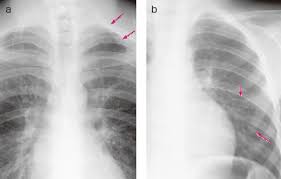

갈비뼈의 미세 손상은 단순 엑스레이(X-ray)로 잘 보이지 않는 경우가 많습니다. 이 경우 CT(컴퓨터 단층촬영) 또는 초음파 검사가 보조적으로 사용될 수 있습니다. 의사는 병력 청취와 촉진검사를 통해 통증 부위를 확인한 뒤, 필요한 경우 정밀 진단을 권합니다.